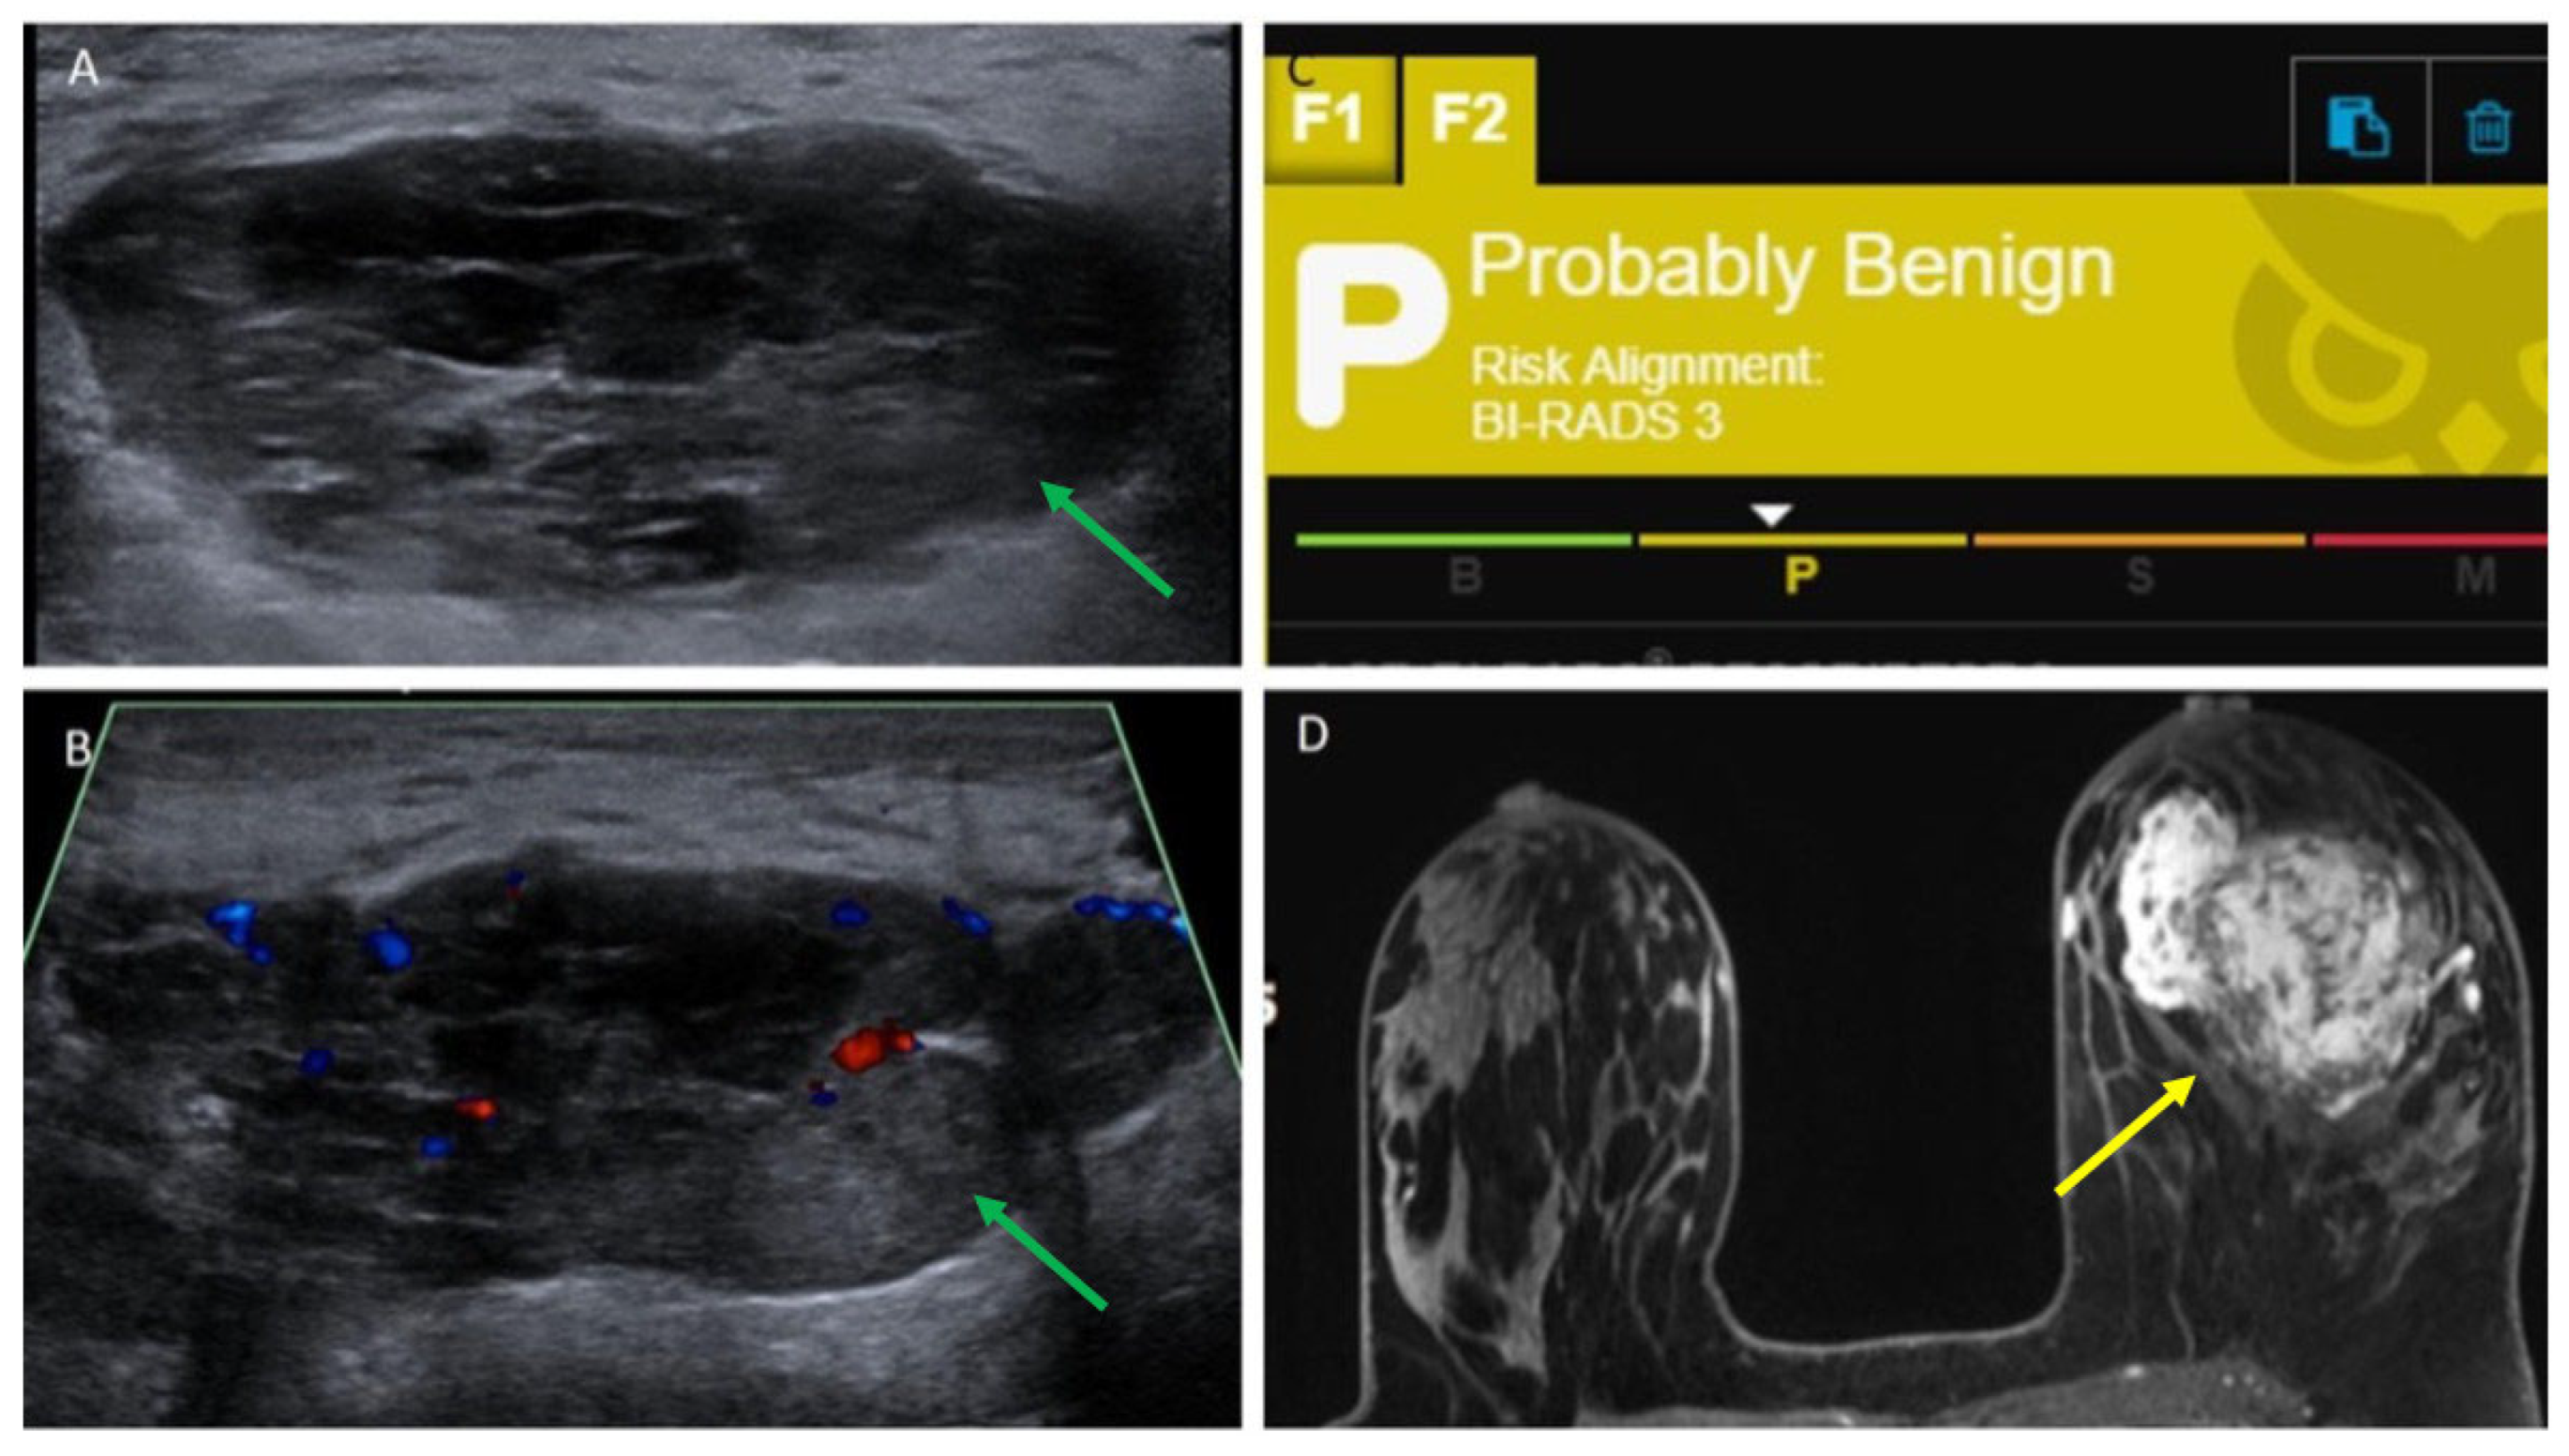

| 16 | 5.5 | Ultrasound core needle biopsy | Irregular, equal-density mass with indistinct margins | Oval, parallel, hypoechoic mass with obscured margins, posterior acoustic enhancement and Doppler flow | Probably Benign, 3 | Irregular mass with irregular margins and heterogeneous enhancement |